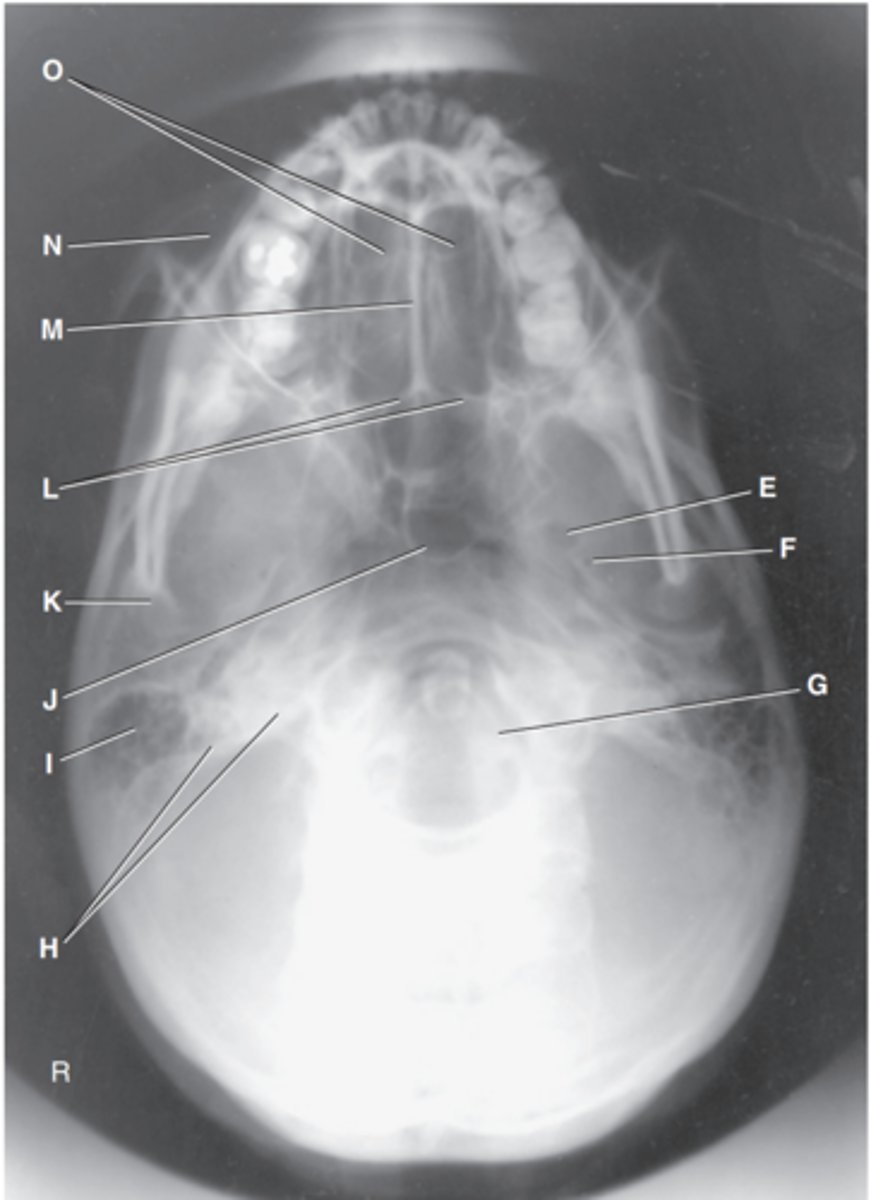

Foramen magnum

Label J

Zygomatic arch

Label A

Palatine process of maxilla

Label B

Horizontal process of palatine bone

Label C

Pterygoid hamulus of sphenoid

Label D

Foramen ovale of sphenoid

Label E

Foramen spinosum of sphenoid

Label F

Foramen magnum

Label G

Petrous pyramid of temporal bone

Label H

Mastoid portion of temporal bone

Label I

Sphenoid sinus in body of sphenoid

Label J

Condyle of mandible

Label K

Posterior border of palatine bone

Label L

Vomer

Label M